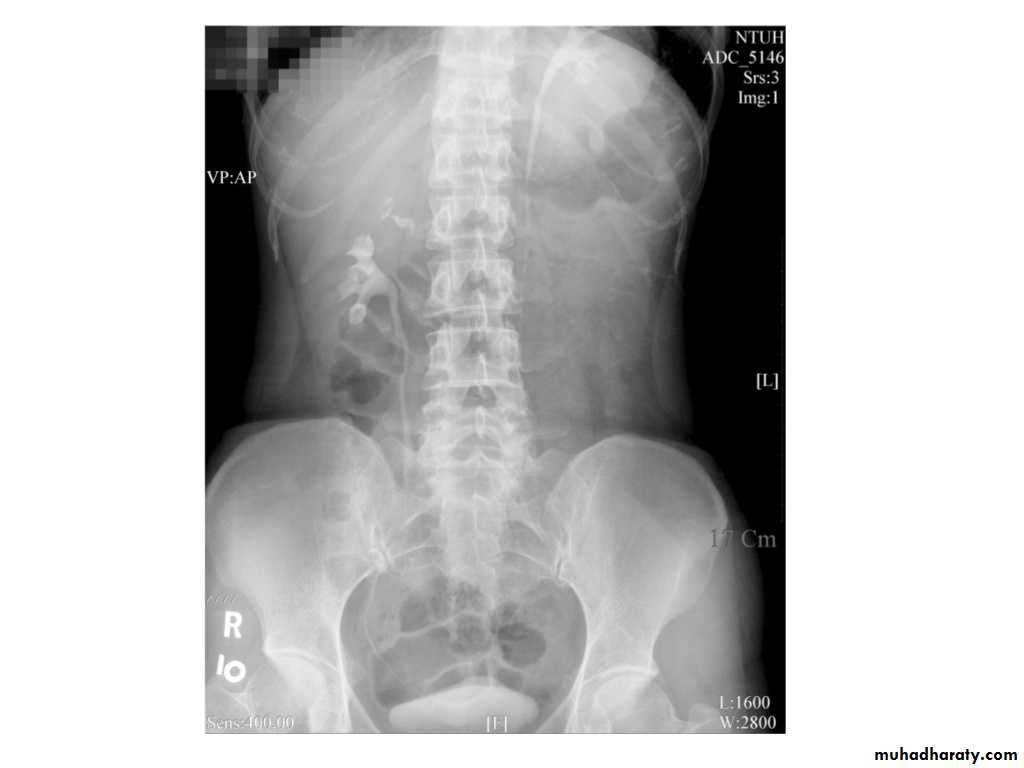

IVU shows

1. The kidneys at low position .2.Close to the spine with long axis parallel to the spine

3. Malrotation manifested by medially directed calyces.

4- The renal pelvis and ureters are anterior and lateral in position.

5- Hydronephrosis and calculi highly associated.